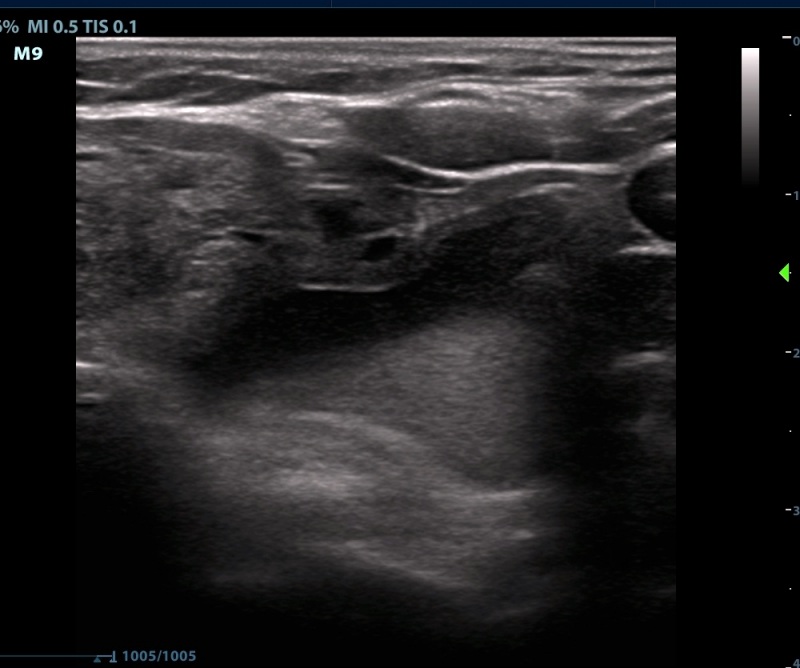

Ultrasonography. The thyroid was echonormal. There were numerous discrete lesions in the right lobe. There was a dominantly solid, echonormal nodule in the isthmus and an almost completely cyst in the left lobe.

28 mL fluid was aspirated from the cyst in the left lobe. Cytology resulted in Bethesda I, cystic fluid only category.